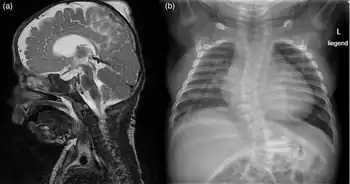

a)) MRI of brain revealed intracranially wide inner and outer cerebrospinal fluid spaces and a very narrow corpus callosum b) X-ray of chest showing cardiomegaly, scoliosis [5]